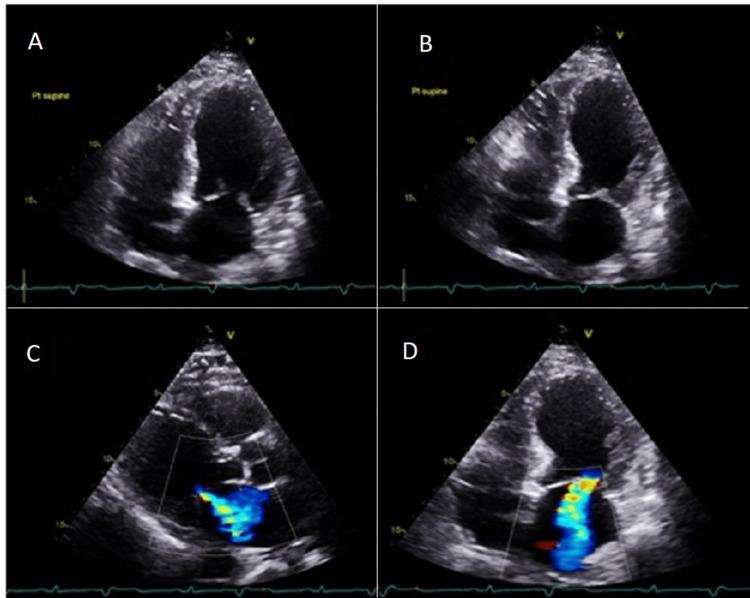

An 84-year-old woman with depression, who witnessed the suicide of a close friend, presented with symptoms of chest pain, palpitations, and cold and clammy extremities. An electrocardiogram showed alternating tachycardia and bradycardia. Urgent transthoracic echocardiogram demonstrated left greater than right ventricular dysfunction, moderate mitral regurgitation, global hypokinesis, and an estimated ejection fraction of 20%. Cardiac catheterization demonstrated non-obstructive coronary artery disease and decreased cardiac output. Findings were consistent with Takotsubo cardiomyopathy complicated with cardiogenic shock, acute mitral regurgitation, and sinus node dysfunction. Management of this patient required the use of a mechanical device intra-aortic balloon pump, and pacemaker insertion for persistent symptomatic arrhythmia. This case highlights the challenging management of potentially fatal acute complications of Takotsubo cardiomyopathy and inadequate data on how to approach them.

一名84岁患有抑郁症的女性,目睹了一位密友的自杀,出现胸痛、心悸以及四肢冰冷潮湿的症状。心电图显示心动过速和心动过缓交替出现。紧急经胸超声心动图显示左心室功能障碍大于右心室,中度二尖瓣反流,整体运动减弱,估计射血分数为20%。心导管检查显示非阻塞性冠状动脉疾病和心输出量减少。检查结果符合应激性心肌病并发心源性休克、急性二尖瓣反流和窦房结功能障碍。该患者的治疗需要使用主动脉内球囊反搏机械装置,并因持续性症状性心律失常而植入起搏器。本病例突出了应激性心肌病潜在致命急性并发症的挑战性管理以及关于如何处理这些并发症的资料不足。